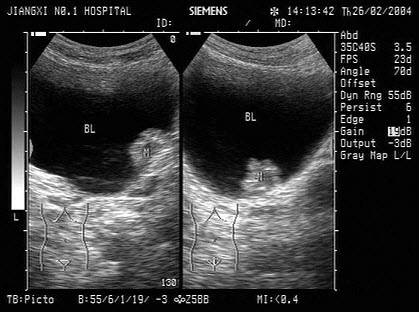

2、单项选择题

下图为宫内孕囊声像图,可见心管搏动,该胎儿至少大于多少周()

A.6周

B.9周

C.10周

D.12周

E.8周